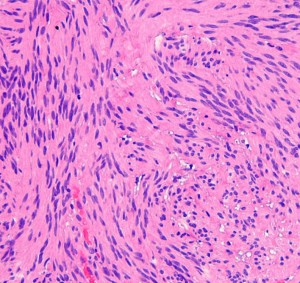

上顎洞癌と間違えるようなもの

三叉神経鞘腫は,頭蓋底の孔(上眼窩裂,正円孔,卵円孔)から眼窩内や頭蓋底,鼻咽腔に伸びることがあります。CTで頭蓋底骨の孔の拡大があることで診断がつきます。bone erosionといって徐々に大きくなる腫瘍の特徴的な所見です。

左上顎癌と間違えそうなMRI画像です。CTでは左の正円孔(黄色の矢印)が辺縁が滑らかに拡大 erosion しているので三叉神経第2枝(上顎神経)の神経鞘腫の診断がつきます。